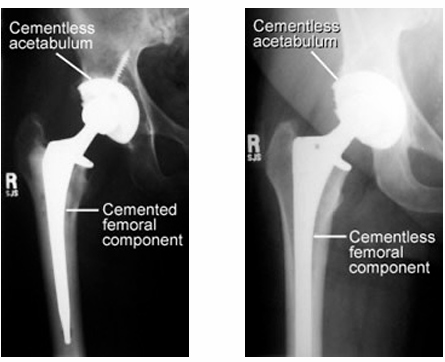

Operation Type - Total Hip Replacement, Prosthesis & Management

Most commonly used prosthesis:

Metal on polyethylene – ball is metal, socket is plastic or plastic lined (polyethylene)

Ceramic on polyethylene – ball is ceramic, socket is plastic or plastic lined (polyethylene)

Ceramic on ceramic - ball is ceramic, socket is ceramic lined

Ceramic on metal - ball is ceramic, socket is metal lined